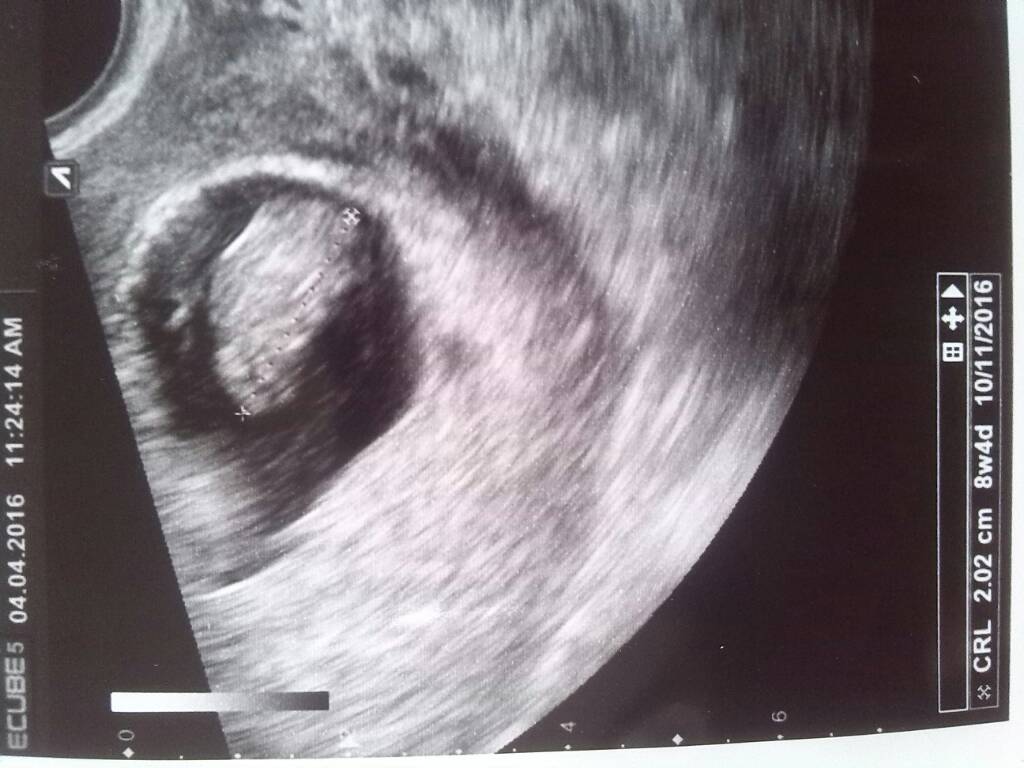

Moj fasol z dzis :-)

Załączniki

• 1459773635056.jpg

1459773635056.jpg

78,1 KB · Wyświetleń: 103